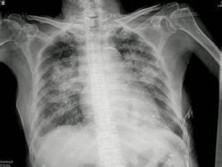

肺栓塞和肺梗死

肺栓塞又称肺血栓塞,是由内源性或外源性栓塞引起的肺循环障碍的临床和病理生理综合征...